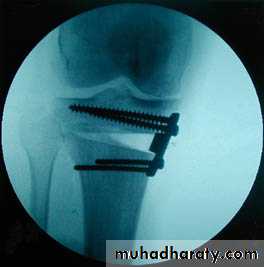

For patient near skeletal maturity (1-2 years) of maturity we can use stapling (internal fixation with staples) of the upper tibial & lower femoral epiphysial plates at the side of overgrowth to allow other side to grow & correct the deformity.

If the above procedure is not applicable we do corrective osteotomy and we should avoid injuring the nearby epiphysis; for varus deformity we do high tibial osteotomy, & for valgus deformity we do supracondylar femoral osteotomy.

• Surgery may be in the form of epiphysial growth arrest (stappling) or by osteotomy.